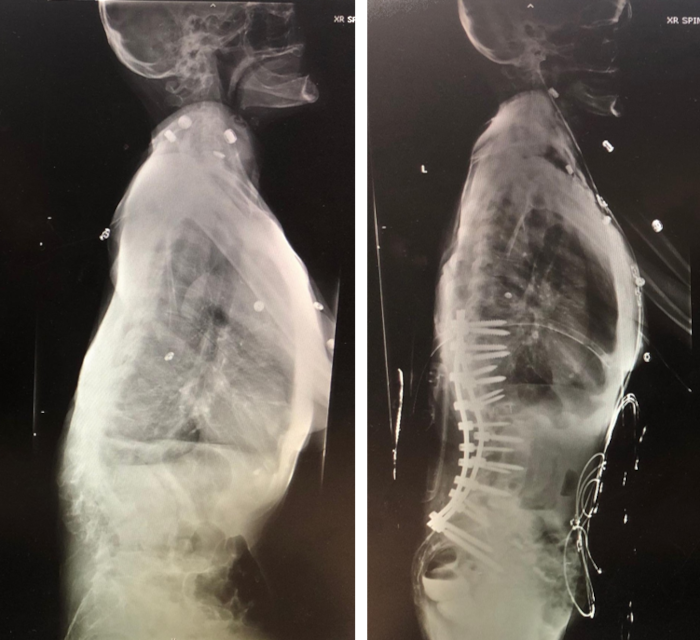

Fortunately, she later met with Dr. Xavier Gaudin who has expertise in the field of scoliosis and spinal deformity. Dr. Gaudin was determined to bring her life back and had a comprehensive treatment plan for her condition. Prior to considering any surgery, she required thorough medical optimization. She began taking Forteo (Teriparatide), a parathyroid hormone to promote bone growth to help her anticipated spinal reconstruction and healing. Additionally, she was started on a nutrition and iron supplementation, and Chantix (Veranicline) for smoking cessation. Following four months of effective optimization, she underwent a T10 to iliac posterior instrumented fusion with L1-2, L2-3 and L3-4 posterior column osteotomies and reduction of her kyphoscoliosis. After uneventful recovery and therapy, she is now able to ambulate fully unassisted and has an increase 7 inches in body height from her spinal reconstruction. She reports her back pain being much improved without requiring any pain medicine, and complete relief of her hip and knee pain. Her postoperative x-rays demonstrated a newly balanced spinopelvic alignment and reduction of her scoliosis curve by greater than 50%. She is to this day fully independent and able to enjoy walks in the park with her grandchildren. The surgery was life changing and brought tears to her eyes.